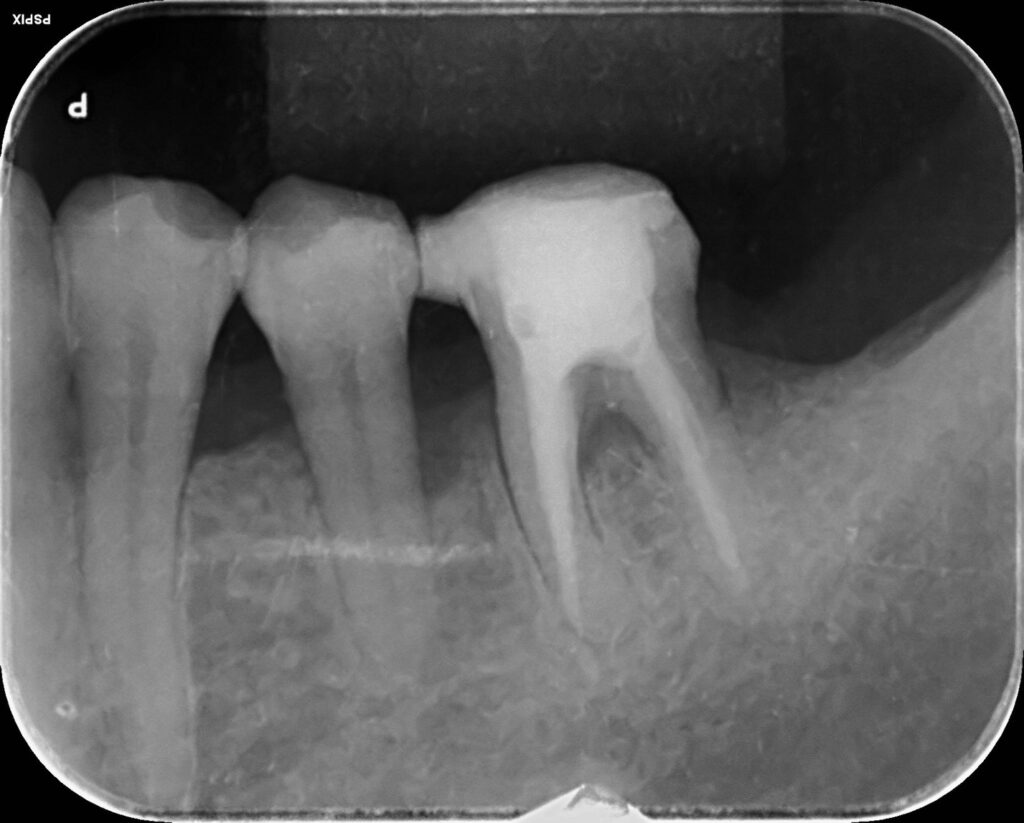

治療前

治療後